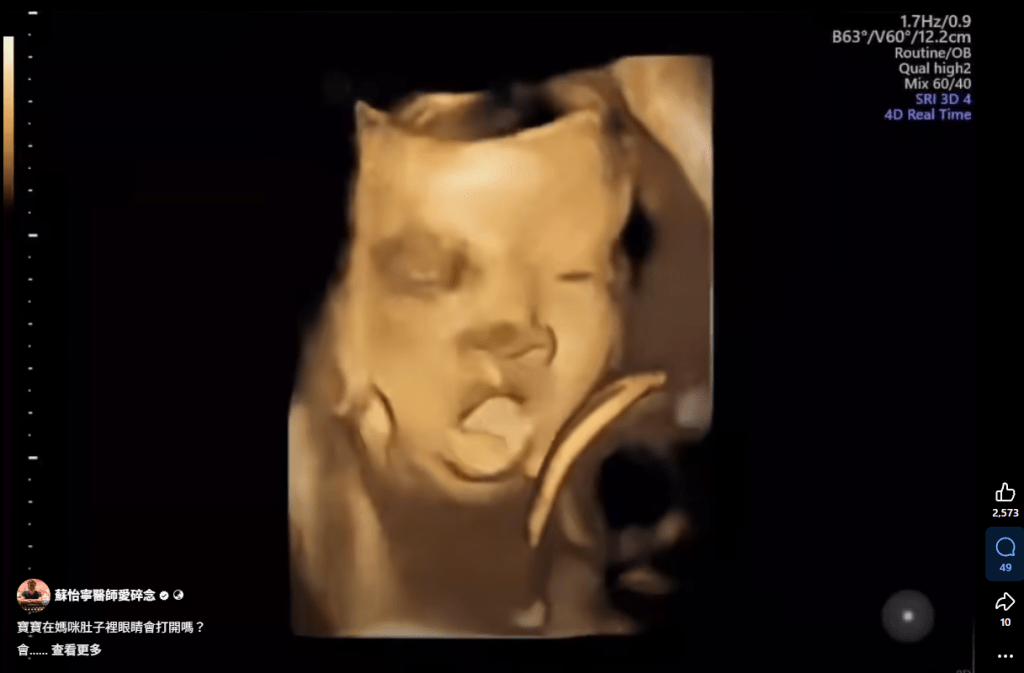

寶寶在媽咪肚子裡眼睛會打開嗎? 寶寶在媽咪肚子裡眼睛會打開嗎? 會 只是不容易被看到 跟人生很多事情一樣 稍縱即逝 不過子宮裡面很暗 所以看不太到什麼 不要問我為什麼要打開 這只是神經發育的一部分 不然你問寶寶 就醬 FB原文討論串 分享此文: 分享到 X(在新視窗中開啟) X 分享到 Facebook(在新視窗中開啟) Facebook 喜歡 正在載入... 相關 在〈寶寶在媽咪肚子裡眼睛會打開嗎?〉中有 1 則留言 Add yours 引用通告: 蘇醫師愛碎念導覽目錄(置頂文) – 蘇怡寧醫師愛碎念 發表留言 取消回覆 Δ